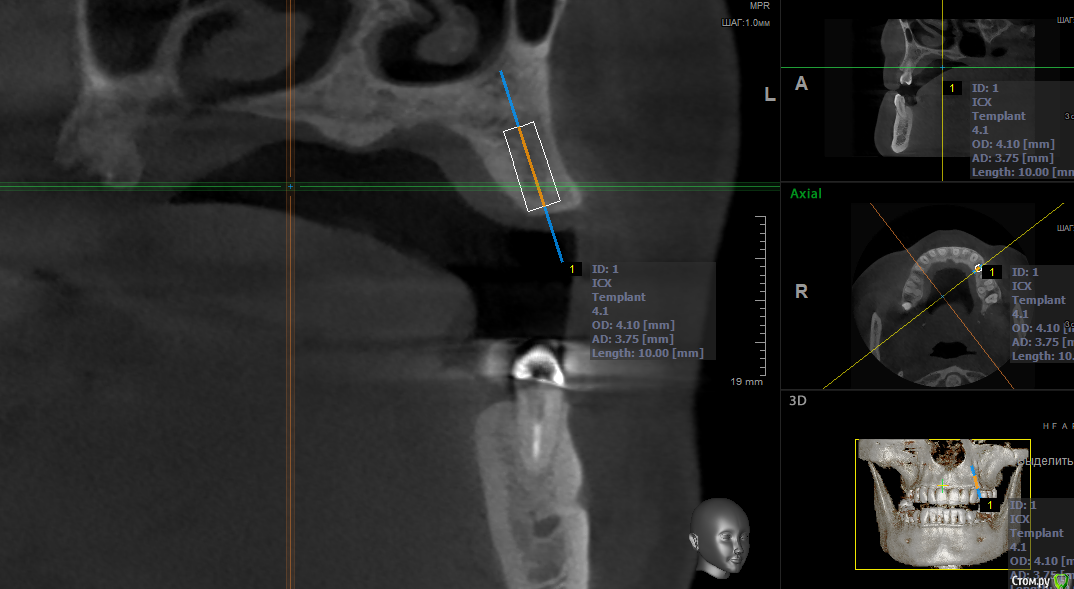

kramer Опубликовано 16 мая, 2018 Поделиться Опубликовано 16 мая, 2018 Коллеги, здравствуйте. Подскажите, пожалуйста, какое положение имплантата будет наиболее оптимальным? Область 24. Ставить под углом и в последствии угловой абатмент или прямо, но с риском для кортикалки? или нечто третье? Ссылка на комментарий

kramer Опубликовано 16 мая, 2018 Автор Поделиться Опубликовано 16 мая, 2018 Срез не верный. Переделал. Как-то так. Ангуляция имеется Ссылка на комментарий

Evikrol Опубликовано 16 мая, 2018 Поделиться Опубликовано 16 мая, 2018 Я бы вот так поставил и подлиннее и на винтовую 5 Ссылка на комментарий

Irouil Опубликовано 16 мая, 2018 Поделиться Опубликовано 16 мая, 2018 Согласен, надо что-то среднее 1 Ссылка на комментарий